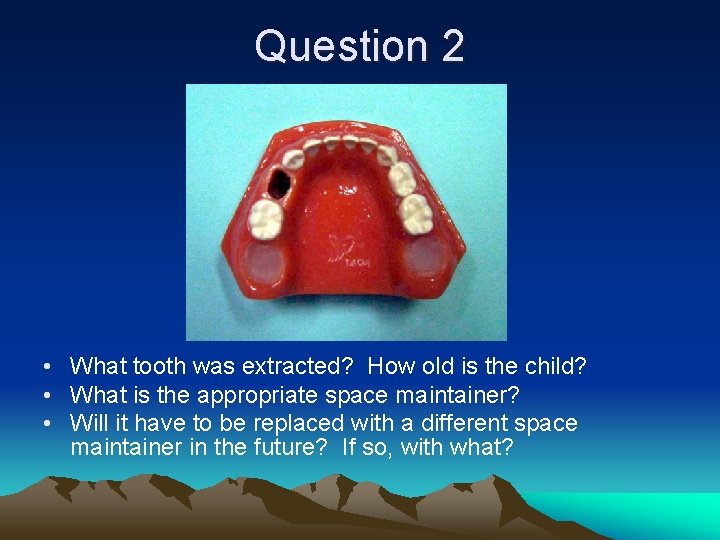

Question 2 • What tooth was extracted? How old is the child? • What is the appropriate space maintainer? • Will it have to be replaced with a different space maintainer in the future? If so, with what?

Question 2 • Tooth #L extracted. 3 -5 y. o. child. • What is the appropriate space maintainer? • Will it have to be replaced with a different space maintainer in the future? If so, with what?

Question 2 • Band/Crown Loop #K-M • May need to be replaced by LLHA later. Tooth #M should exfoliate prior to eruption #21.